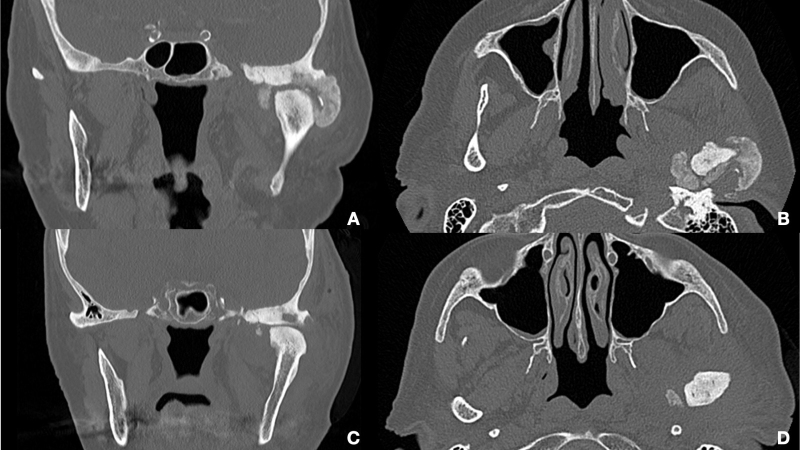

Background: Calcium pyrophosphate dihydrate deposition disease (CPPD) is a metabolic disease resulting in acute arthritis. CPPD often affects joints containing fibrocartilage. The purpose of this review is to examine the clinical presentations, prevalence, and treatment modalities associated with CPPD when it affects the temporomandibular joint (TMJ).

Results: A systematic review of literature identified 64 papers, reaching a total of 74 cases of CPPD of the temporomandibular joint TMJ. CPPD is a condition that typically affects middle-aged or older patients, with an average age of around 60 at the time of diagnosis. Females are affected more frequently than males. Most cases involve unilateral TMJ involvement, and common symptoms include pain, reduced mouth opening, and swelling. Different papers also describe severe stages of the invasion of muscles, parotid gland, and even brain structure. Surgery has the preferred treatment option for most Authors and is mandatory for late-stage lesions. The recurrence rate is extremely low.

Conclusions: CPPD is an uncommon, locally invasive, and typically benign condition that rarely affects the TMJ. Distinguishing CPDD in the TMJ from other neoplasms poses diagnostic challenges. A definitive diagnosis necessitates histological examination and quantitative microanalysis. In our patient, successful excision of CPDD in the TMJ was achieved using an external approach.